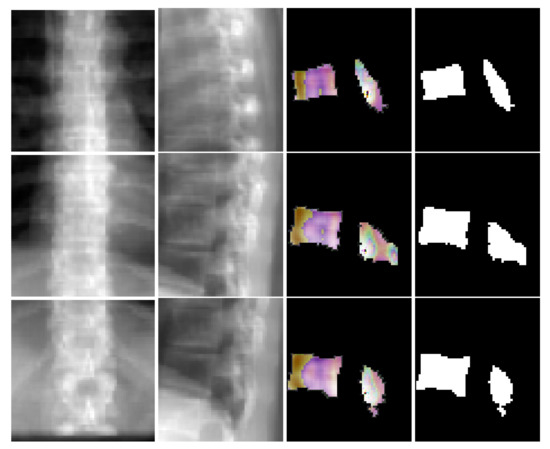

Figure 6 depicts coronal and sagittal image patches from three vertebrae, mid-slice of the resulting estimated displacement field and vertebral shape. In the estimated displacement field the brighter colors indicate greater displacements. Figure 7 shows an example point cloud (with 2048 points) from the predicted and ground truth shapes, along with a point-wise Chamfer distance map. Observe that the vertebra’s posterior region (vertebral process) is hardly visible in the image inputs. In spite of this, TransVert+ was able to reconstruct the 3D shape of vertebral processes. To calculate the Chamfer distance map for each point in the reconstructed vertebra’s point cloud, the nearest point in the ground truth point cloud is found and the square of distance is depicted. Figure 8 illustrates a 3D spine reconstruction based on 2D DRRs.

Figure 6. Visualization of coronal and sagittal image patches from three vertebrae. First and second columns are the coronal and sagittal image patches, third column shows one slice of the predicted deformation field and last column is the corresponding slice in the resulting shape.